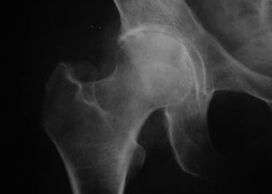

Artrosia duen artikulazio baten agerpena

Koxatrosia, aldaka artikulazioko artrosia

Gaixotasun honekin, artrosiaren irudi kliniko klasikoa ikusten da.

Koxartrosiaren lehen sintoma jarduera fisikoaren ondoren aldaka artikulazioan ondoeza da.

Koxartrosi progresiboarekin, mina areagotu egiten da, zurruntasuna eta mugikortasun mugatua agertzen dira.

Koxartrosi forma larria duten pazienteek kaltetutako gorputz-adarra sobratzen dute, zapaltzea saihestuz, eta geldirik dauden bitartean, mina gutxien sentitzen den posizioak aukeratzen dituzte.